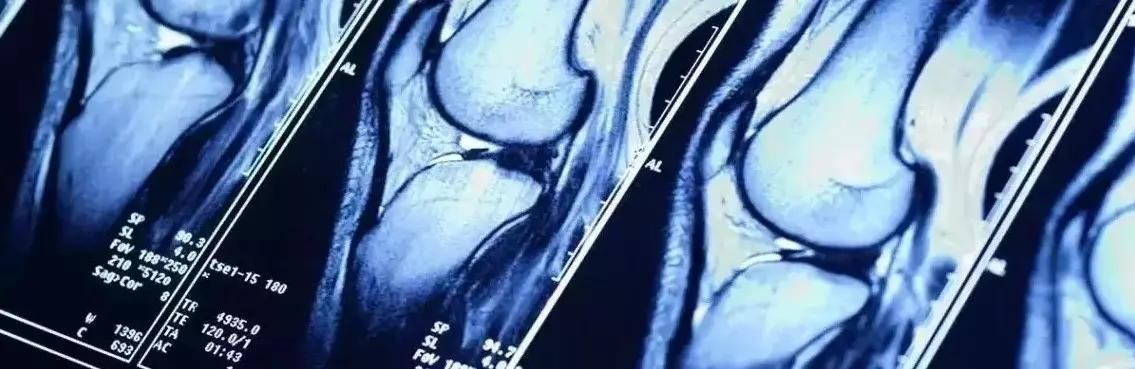

Sportowcy, mimo że najczęściej nie zmagają się z nadwagą, również są narażeni na chorobę zwyrodnieniową stawów. Nasze stawy nierzadko ulegają nadmiernemu obciążeniu podczas uprawiania sportu. Za długie i zbyt intensywne treningi, brak odpowiedniej przerwy na regenerację (przetrenowanie organizmu), bagatelizowanie bólu pojawiającego się podczas ćwiczeń, uprawianie sportów wyczynowych (ekstremalnych) – to wszystko sprawia, że stawy sportowców są stale narażone nie tylko na chwilowe kontuzje, lecz także na negatywne efekty długofalowe, np. w postaci choroby zwyrodnieniowej stawów. Zmianom zwyrodnieniowym ulegają głównie stawy biodrowe, kręgosłup oraz stawy kolanowe, czyli wszystkie te, które przenoszą duże obciążenia. Należy jednocześnie podkreślić, iż wtórna postać osteoartrozy dotyka nawet osób przed trzydziestym rokiem życia. Choroba zwyrodnieniowa stawów może zatem stanowić poważne ryzyko dla aktywnie trenujących. Jak w takim razie zminimalizować ryzyko wystąpienia problemów ze stawami, kiedy jesteśmy osobami aktywnymi sportowo lub nawet zawodowymi sportowcami? Czy można odpowiednio zadbać o stawy podczas uprawiania sportu?